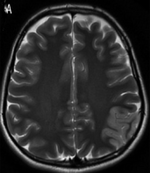

T2 Weighted Imaging

- Highlights CSF

- Good for identifying tissue edema around pathologic areas

- Fluid is hyperintense (reverse of T1)

- Tissue tends to be more hypointense